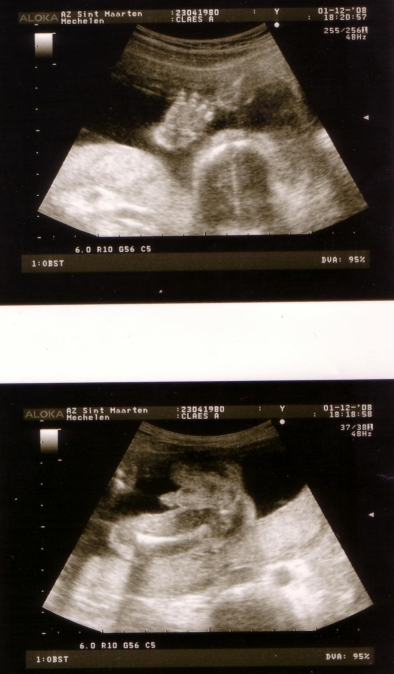

Geen woorden nodig 1 December 2008 / Wiz, ZwangerUncategorized Ja, het mysterie is opgelost. De beelden spreken voor zich!!! De mama en de papa zijn in de wolken en Liv … die zegt alleen maar “dank u” Discover more from Annelyse Subscribe to get the latest posts sent to your email. Type your email… Subscribe

Annelyse 1 December 2008 at 21:05 Allé, nen tip dan 😉 de onderste echo kijkt recht tussen de benen (van onderuit gezien) Reply

de onderste echo kijkt recht tussen de benen (van onderuit gezien)

annava 1 December 2008 at 21:27 ik zie het niet maar omdat het onder Wiz getagd sta ga ik er van uit dat het een jongentje is. Wel, een dikke proficiat! Reply

Zita 1 December 2008 at 22:40 Ik ben ook niet bijster onderlegd in ‘t interpreteren van echo’s. Gelukkig waren er de tags! Liv krijgt een broertje! 🙂 Reply

Liv krijgt een broertje! 🙂